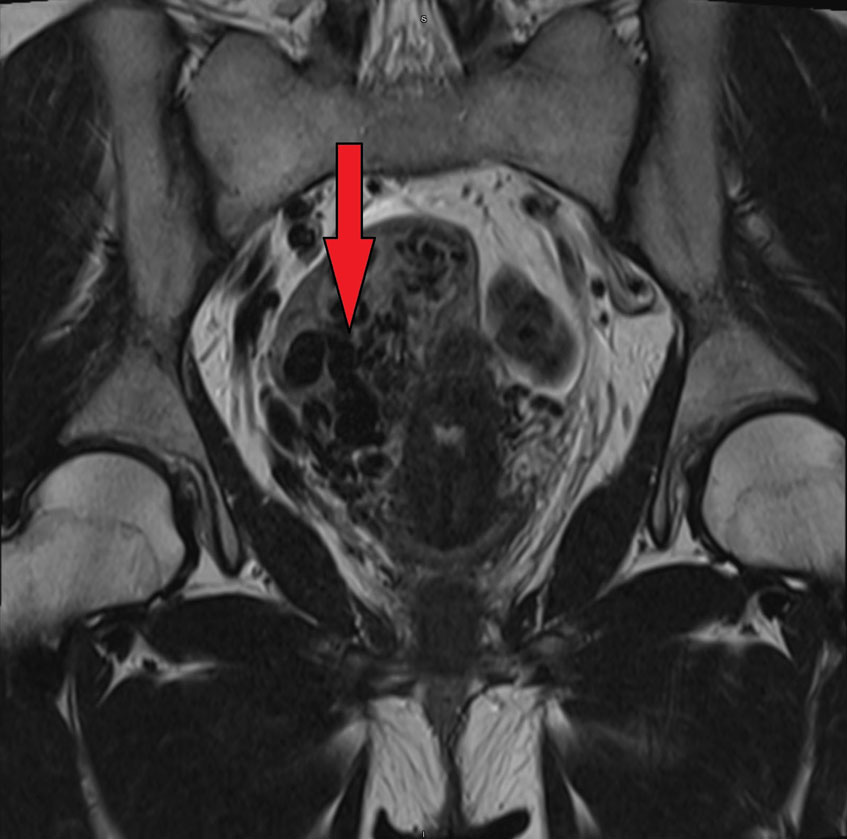

BS.CKII Thi Văn Gừng, Trưởng đơn vị Hình ảnh học can thiệp – Trung tâm Chẩn đoán hình ảnh & Điện quang can thiệp, kiêm Phó Giám đốc Trung tâm Can thiệp mạch, Bệnh viện Đa khoa Tâm Anh TP HCM cho biết, sau khi siêu âm, chụp cộng hưởng từ vùng chậu chẩn đoán cho thấy chị Nga có 2 tổn thương. Bên cạnh khối u buồng trứng phải kích thước khoảng 3.5 cm, nghi ngờ u quái buồng trứng, bệnh nhân còn có khối tổn thương lớn mặt sau dưới thanh mạc cơ tử cung, kích thước khoảng 6 cm, có nhiều mạch máu bên trong, nghi ngờ thông nối động tĩnh mạch (arteriovenous malformation-AVM) trong cơ tử cung.

BS.CKII Nguyễn Bá Mỹ Nhi, Giám đốc Trung tâm Sản Phụ khoa Bệnh viện Đa khoa Tâm Anh TP HCM cho biết, AVM gây ra bởi sự tăng sinh các động mạch, tĩnh mạch với sự hình thành của thông nối trực tiếp giữa động mạch, tĩnh mạch không qua mao mạch. Đa số AVM ở tử cung thường mắc phải sau sảy thai, thủ thuật như nạo phá thai, mổ lấy thai… Một số trường hợp hiếm gặp là AVM bẩm sinh như trường hợp bệnh nhân Nga là xuất phát phát từ sự bất thường phát triển phôi thai.

Bác sĩ Gừng cho biết thêm, dị dạng mạch máu tử cung bẩm sinh của bệnh nhân lớn, được xếp nguy cơ cao gây chảy máu ồ ạt nếu bị vỡ vào trong ổ bụng hoặc xuất huyết tử cung nặng. Khối này được cấp máu từ rất nhiều nhánh có nguồn gốc động mạch chậu trong hai bên, bác sĩ phải chọn lọc sâu vào nhánh động mạch cấp máu cho dị dạng, bơm tắc cẩn thận để tránh dội vào nhánh động mạch lành nuôi tử cung, nhánh mạch máu nuôi buồng trứng.